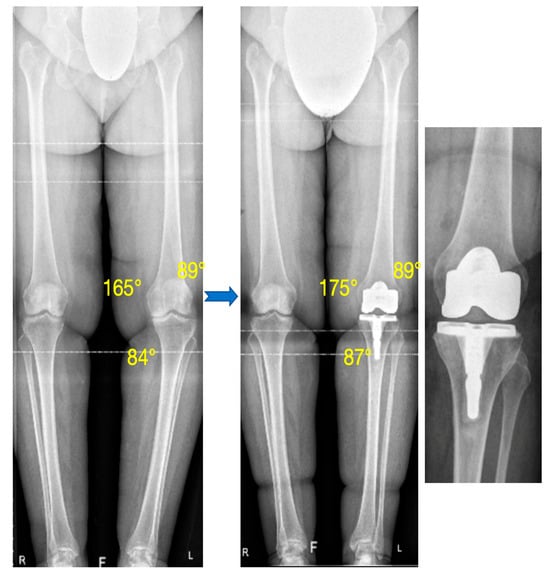

3.1. Alignment

| HKA (°) (mean ± SD) [Min; Max] | 170.2 ± 3.9 [163.5; 179] | 177.4 ± 2.2 [172; 182] | <0.0001 |

| OUTLIERS: HKA < 175° | - | 4 (8.9%) | - |

| mMDFA (°) (mean ± SD) [Min; Max] | 91.3 ± 2 [87; 94] | 91.1 ± 1.5 [88; 94] | 0.76 |

| OUTLIERS: mMDFA > 95° | - | 0 | - |

| OUTLIERS: mMDFA > 93° | - | 1 (2.2%) | - |

| MPTA (°) (mean ± SD) [Min; Max] | 85.7 ± 2.1 [82; 90] | 87.4 ± 1.8 [83; 90] | <0.0001 |

| OUTLIERS: MPTA < 85° | - | 2 (4.4%) | - |

| OUTLIERS: MPTA < 87° | - | 11 (24.4%) | - |

| JLCA (°) (mean ± SD) [Min; Max] | 6.2 ± 2.2 [1; 12] | - | - |

| JLO (°) (mean ± SD) [Min; Max] | −0.9 ± 2.4 [−7; 5] | 0.9 ± 1.7 [−2; 4] | 0.0002 |

| OUTLIERS JLO > 3° | - | 3 (6.7%) | - |

| Slope (°) (mean ± SD) [Min; Max] | 81.7 ± 3.1 [74; 89] | 86.8 ± 1.8 [83; 91] | <0.0001 |

| OUTLIERS Slope < 80° | - | 0 | - |

| Difference Post–Pre of Posterior Femoral offset (mm) (mean ± SD) [Min; Max] | 1.9 ± 1 [0.09; 5.4] | - |